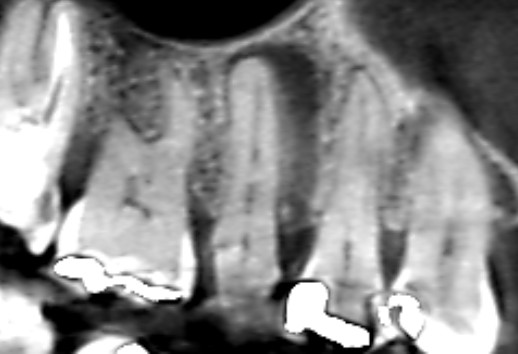

根管治療6ヶ月後のCT画像です。根の横にみられた長い影が消失し、歯槽骨が再生しています。